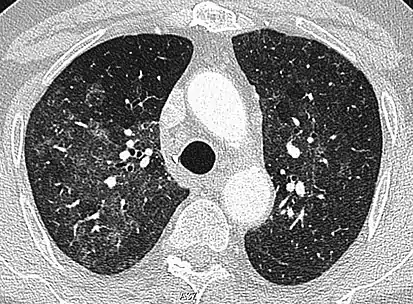

CT image showing diffuse GGOs throughout both lungs. An abscess is also noted in the right lung (screen left). - Adenocarcinoma in situ of the lung

Diffuse

The diffuse pattern typically refers to GGOs in multiple lobes of one or both lungs. Broadly, a diffuse pattern of GGO can be caused by displacement of air with fluid, inflammatory debris, or fibrosis. Cardiogenic pulmonary edema and ARDS are common causes of a fluid-filled lung. Diffuse alveolar hemorrhage is a rarer cause of diffuse GGO seen in some types of vasculitis, autoimmune conditions, and bleeding disorders.[6]

Inflammation and fibrosis can also cause diffuse GGOs. Pneumocystis pneumonia, an infection typically seen in immunocompromised (e.g. patients with AIDS) or immunosuppressed individuals, is a classic cause of diffuse GGOs. Many viral pneumonias and idiopathic interstitial pneumonias can also lead to a diffuse GGO pattern. Radiation pneumonitis, a side effect of pulmonary radiation therapy, can lead to pulmonary fibrosis and diffuse GGOs.[6]